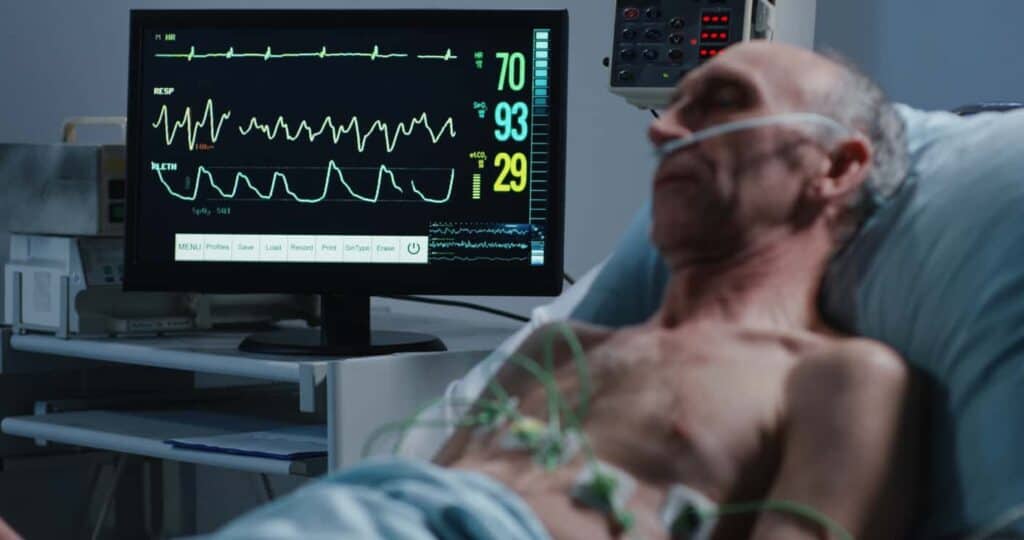

What Happens In Your Brain During A Near-death Experience

www.yourlifechoices.com.auWhat happens in your brain during a near-death experience …

www.yourlifechoices.com.auWhat happens in your brain during a near-death experience …

Conscious-Like Neural Activity Seen In Dying Brains May Explain Near

www.iflscience.comConscious-Like Neural Activity Seen In Dying Brains May Explain Near …

www.iflscience.comConscious-Like Neural Activity Seen In Dying Brains May Explain Near …

What Near-Death Experiences Reveal About The Brain | Scientific American

www.scientificamerican.comWhat Near-Death Experiences Reveal about the Brain | Scientific American

www.scientificamerican.comWhat Near-Death Experiences Reveal about the Brain | Scientific American